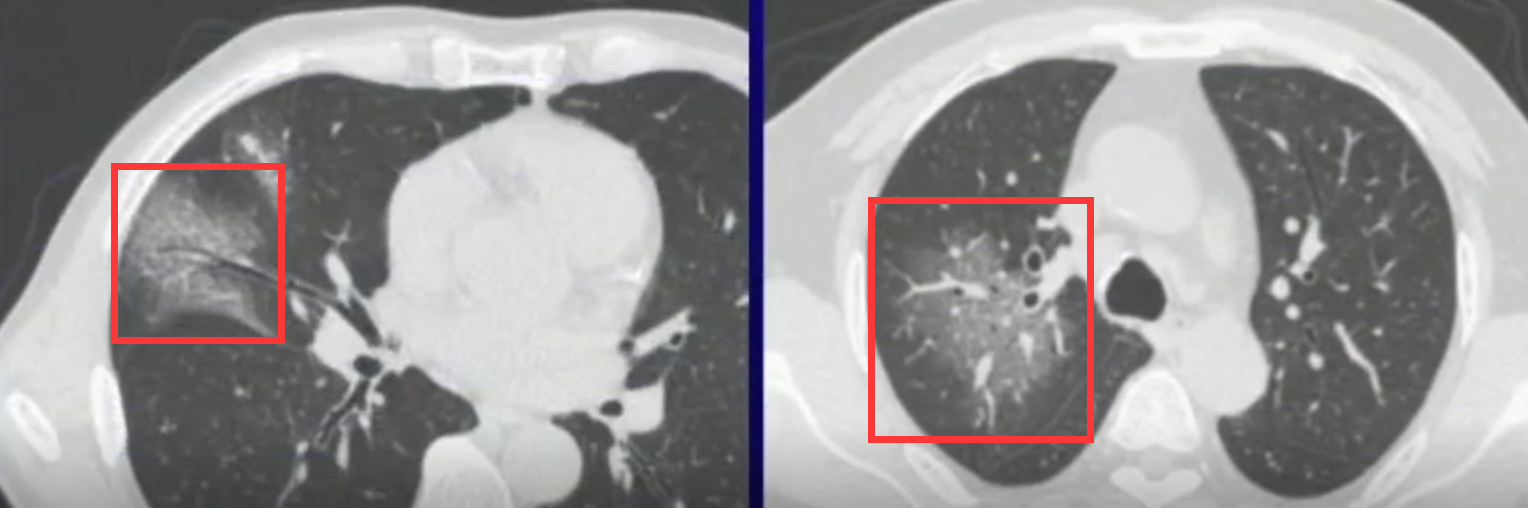

烟花式扩散

新型冠状病毒大小为60-140纳米,而肺泡孔的尺寸则为10-15微米。由此可见,肺泡孔比新冠病毒大约1到2个数量级。因此,在传播机制上,新冠状病毒主要通过肺泡孔进行扩散。磨玻璃影的表现通常呈现中心向四周扩散的特征,并且由于较少受到小叶阻挡,在形态上中间部分较为连通(见图2)。与之相比,细菌则较大,在传播过程中主要通过细支气管进行扩散,并沿着这些气管分布排列。

图2.烟花式扩散

细小网格或者条状影

如果具备前两个特征,并且对磨玻璃影区域进行详细观察(源自广东省人民医院放射科行政副主任赵振军主讲《新型冠状病毒感染CT早期诊断和鉴别诊断》),则可能观察到如图所示的微小网格结构(来自上述报告)。这些发现通常反映在人读片时的观察中。然而,在机器识图的过程中又是如何依据哪些特征进行判断的呢?这个问题值得深入探讨。

图3.细小网格影